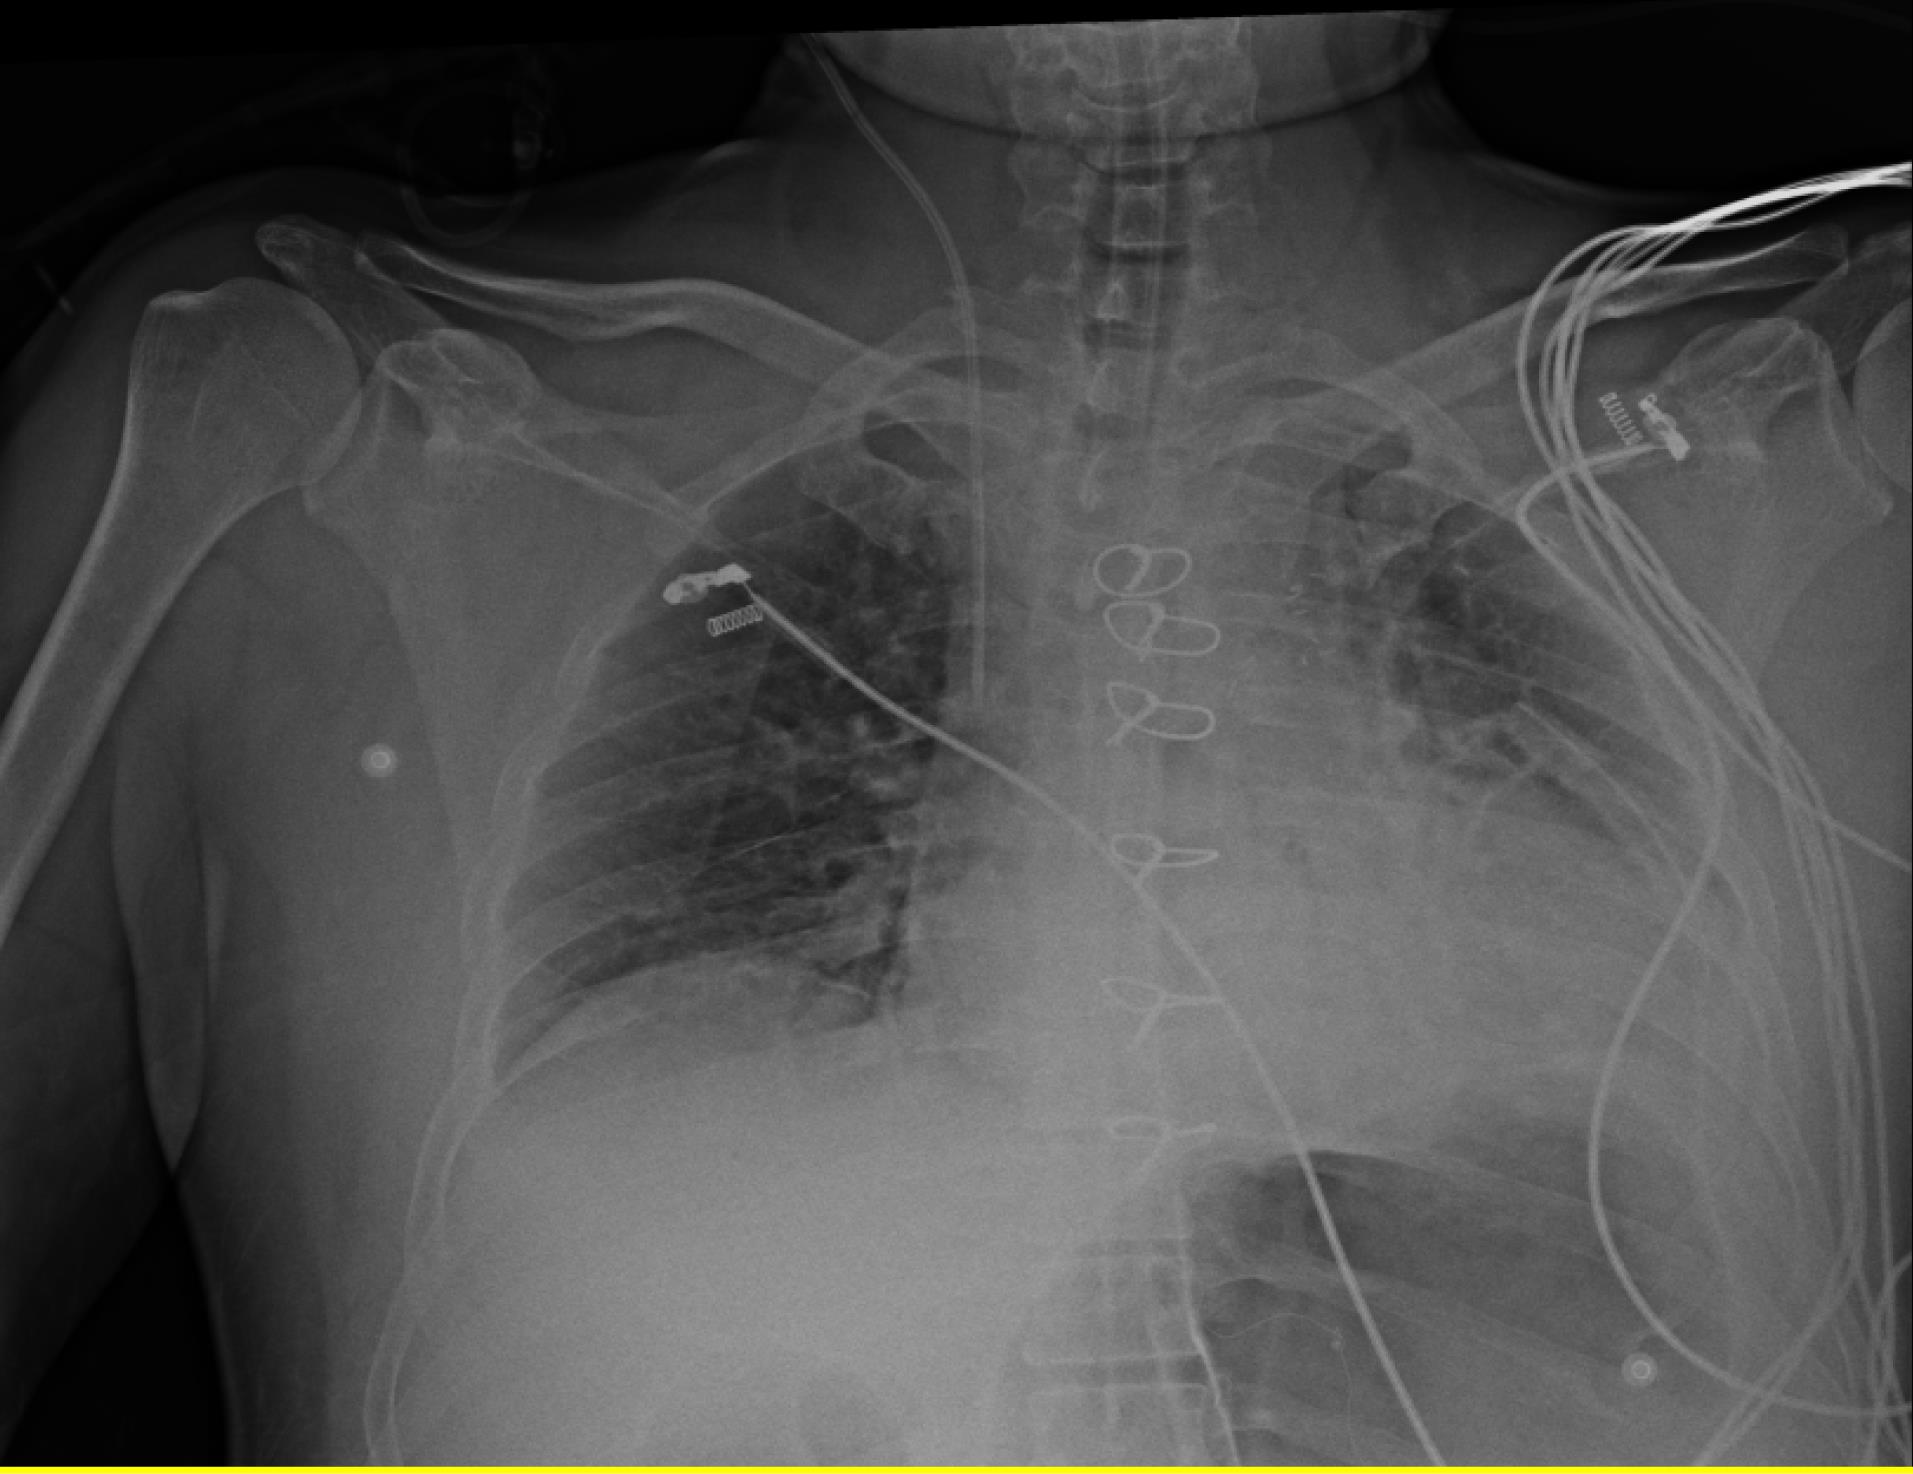

After preliminary checks, demographic data including Age, gender, weight (kg), height (cm), and body mass index (BMI) (kg/m2) were gathered. All 100 CVC were inserted in the internal jugular vein with disinfection method with alcoholic chlorhexidine antiseptic for skin preparation, then cvc was fixed according to the Press formula by a cardiac anesthesiologist in the operating room (OR). According to Peres’ formula, the depth of CVC insertion should be height/10 cm for the right internal jugular vein (IJV), after fixation Chest radiography was performed for patients in the supine position, and the tip position of the catheter was assessed according to the distance between the CVC tip and the carina. We measured the distance between the carina and CVC and recorded it as a Distance variable. One centimeter distance from the carina (higher and lower) is the proper CVC tip position, and other patients were in the wrong CVC tip position and cvc was fixed in correct depth. All of the study demographic and variables related to surgery accompanied by the result of chest radiography were gathered and inserted into the patient list. Figure 1 shows the chest radiography of one patient with incorrect CVC tip insertion. Figure 2 landmarked the proper position of CVC tips according to the carina location on the chest radiography. Figure 3 shows the Bland Altman plot for the Peres estimation and the actual place. The x-axis represents the mean of the Peres estimation and the actual place, while the y-axis shows the difference between the two. The plot includes a red line indicating the mean difference (or bias) between the estimations and actual values, with the blue lines representing the 95% limits of agreement (mean difference ± 1.96 standard deviations). Each point represents an individual data pair, illustrating the variability between the estimation and actual place across different values. This plot is used to assess the agreement between the two methods.

Figure 2.

landmarking of correct CVC tip location according to carina in patient with incorrect CVC tip position according to Peres formula